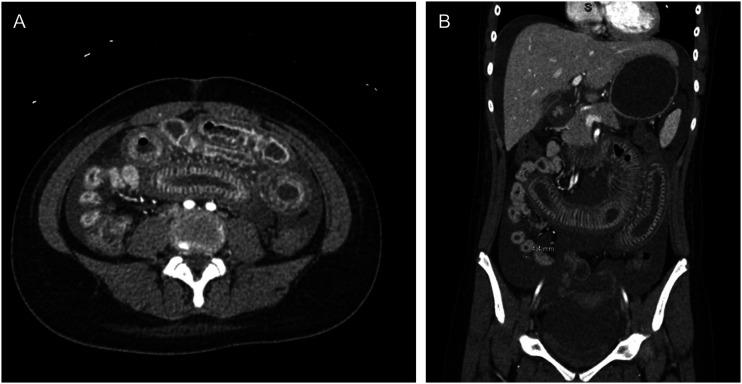

Abstract Image